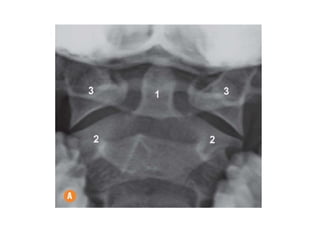

INCIDÊNCIA COLUNA CERVICAL

ESTRUTURAS MAIS DEMONSTRADAS: Corpo e dente de C2 (ÁXIS), corpo

de C1 (ATLAS)